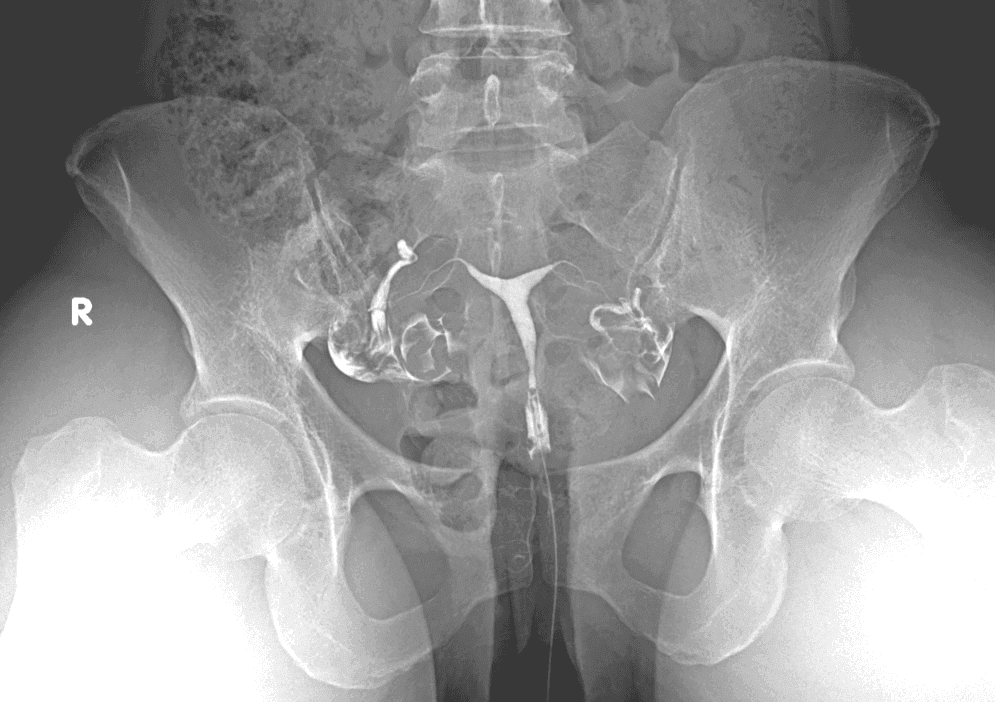

La histerosalpingografía (HSG) es un estudio con medio de contraste y rayos X que ayuda a valorar la cavidad uterina y si las trompas son permeables. Es una herramienta muy útil en la evaluación de fertilidad, siempre con indicación médica.

- Muestra la cavidad uterina y el paso del contraste.

Se introduce un catéter fino e inyecta contraste de manera controlada mientras se toman radiografías.

Toma de imágenes

Un radiólogo interpreta las imágenes para apoyar a tu médico en la toma de decisiones.